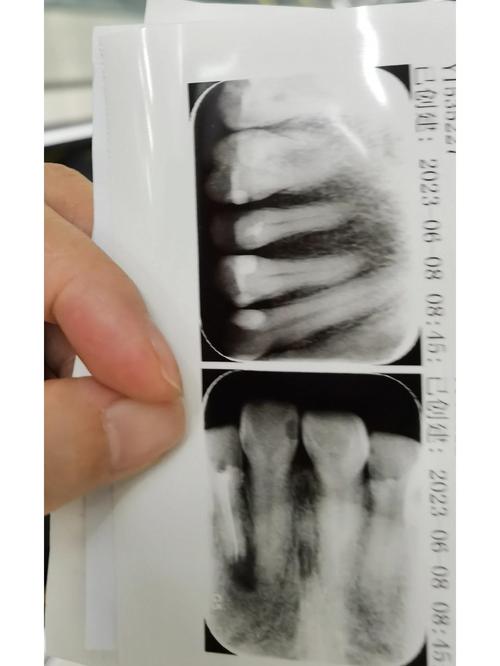

(图片来源网络,侵删)

(图片来源网络,侵删)作为国家级医院,301口腔科配备了国际顶尖的诊疗设备,如CBCT(锥形束CT)、显微镜(用于根管治疗)、口内扫描仪、数字化种植和正畸导航系统等,这为精准诊断和高效治疗提供了硬件保障。

- 资料齐全:如果之前在其他地方看过病,务必带上所有的病历、X光片、CT片等资料,方便医生快速了解病情。